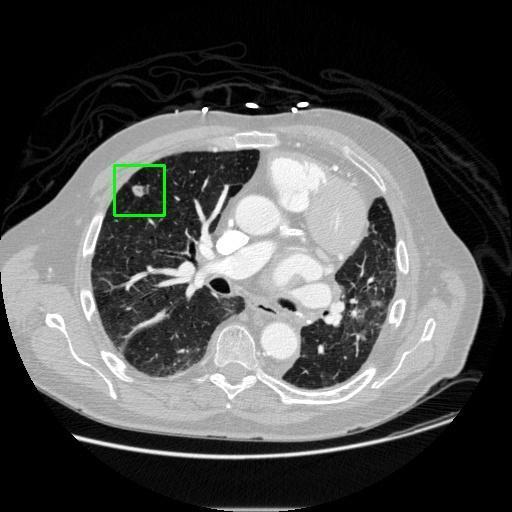

We developed an AI-based system using deep learning models for analyzing lung CT scans to detect and classify pulmonary nodules. We chose the YOLOv11 architecture for its enhanced object detection capability and adapted it specifically for medical imaging, incorporating pixel-level precision and severity classification.

Classification into three severity levels with colored bounding boxes.

Successfully built and deployed an AI model (YOLOv11) capable of detecting lung nodules in CT scans with high accuracy and real-time performance.

Achieved ~0.90 mAP@0.5 on validation data, showing strong object detection capabilities even on complex medical images.

Designed a severity classification system that categorizes nodules into null, moderate, and severe using colored bounding boxes, assisting in rapid clinical decision-making.